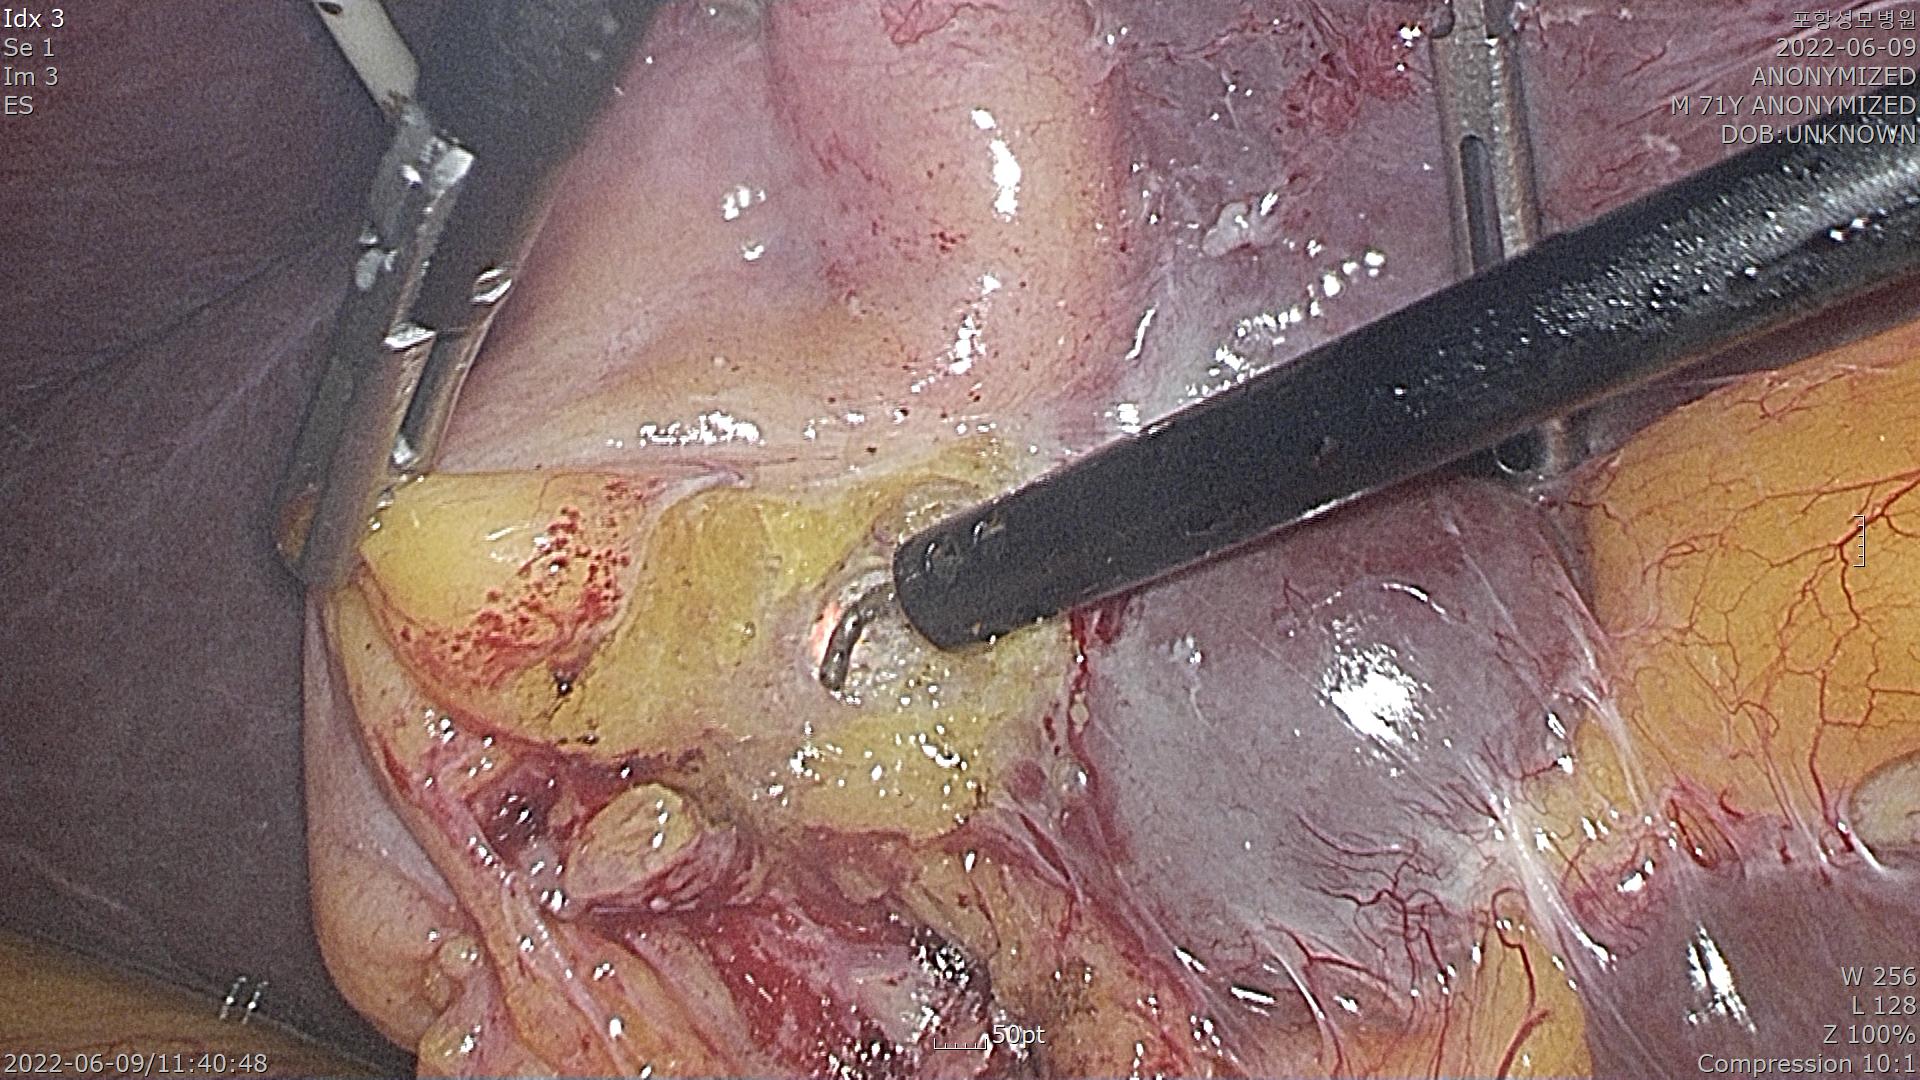

PTGBD가 확인되고 있고 오랜 염증으로 복강내 조직들이 유착이 심합니다.

조심스럽게 담낭을 간후벽에서 제거하고 있습니다.

엔도루프를 이용하여 담낭관을 결찰합니다.

담낭을 잘라냅니다.